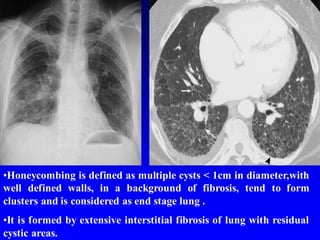

•Honeycombing is defined as multiple cysts < 1cm in diameter,with

well defined walls, in a background of fibrosis, tend to form

clusters and is considered as end stage lung .

•It is formed by extensive interstitial fibrosis of lung with residual

cystic areas.